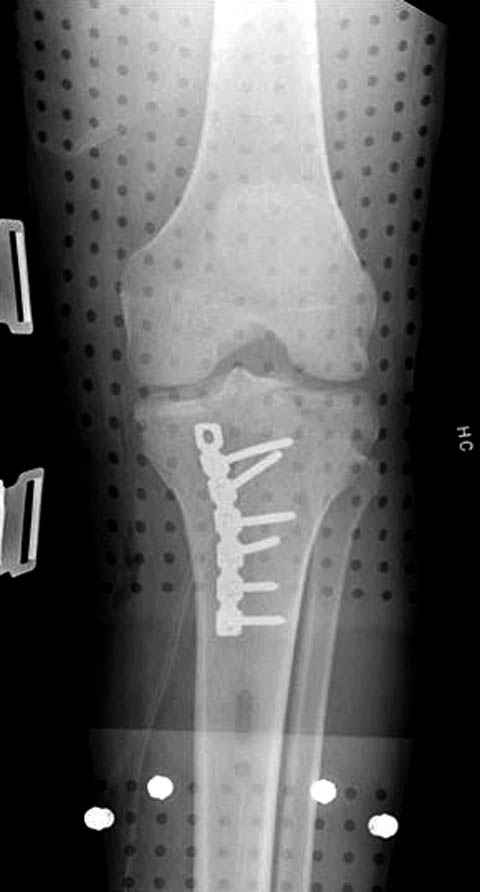

Надеюсь, представленные снимки разных случаев помогут разобраться в тактике, и критика примется без личной обиды.

Имя     : 12 Med plateau fx.JPG

Тип     : image/jpeg